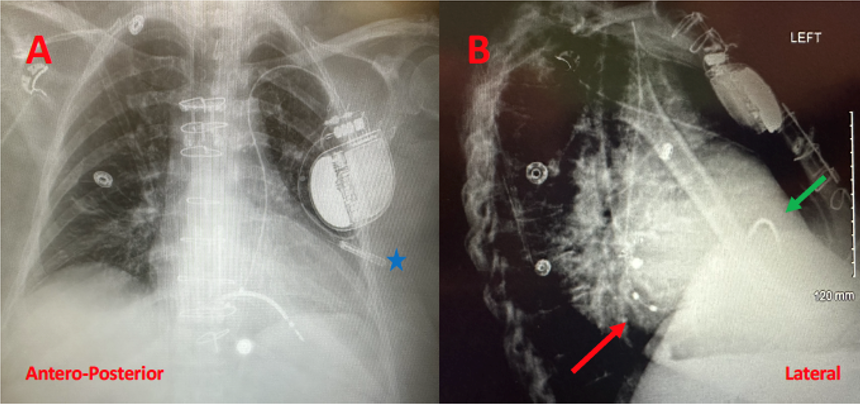

The outpatient procedure was performed under conscious sedation in the electrophysiology lab. Intraoperatively, a standard incision was made in the left delto-pectoral groove and access into the left axillary vein was obtained using ultrasound guidance. A J-tipped wire was advanced under fluoroscopy. At this point, it was evident that the wire did not cross the midline of the chest to enter the superior vena cava, but rather passed from the left subclavian vein into a persistent left superior vena cava (PLSVC) into the coronary sinus (CS) and then into the right atrium (RA). This was confirmed on right and left anterior oblique views. An access sheath was advanced and a DX ICD lead (Pamira S DX 64/15, 15 cm spacing from lead tip to dipole) was advanced via the sheath, into the PLSVC, CS, and into the RA. Using a manually shaped stylet, the lead was prolapsed across the tricuspid valve into the right ventricle (RV) and the helix deployed. Testing of the lead showed appropriate sensing, pacing threshold, and impedance. The atrial sensing dipoles were on the floor of the CS with appropriate P-wave sensing. The sheath was split, and the lead was secured and connected to the device. Repeated testing showed proper sensing of both atrial and ventricular signals (far-field sensing of the ventricle was detected by the atrial dipoles but appropriately labeled by the device). The procedure was completed in under one hour. A postoperative chest x-ray was performed in 2 views (Figure 3).

This PLSVC drained into the RA by way of a dilated CS. In this setting, placing a defibrillation lead presents some technical challenges to the implanting physician. It was imperative that the atrial dipoles of the DX ICD lead be properly situated in the RA for optimal device performance. An alternative approach would be to implant the device in the right chest, after ensuring the presence of a right-sided SVC, possibly utilizing a venogram via a right arm intravenous line. In this case, considering an incision and ICD pocket were already created on the left chest, it was decided to proceed with ICD implant via the PLSVC.